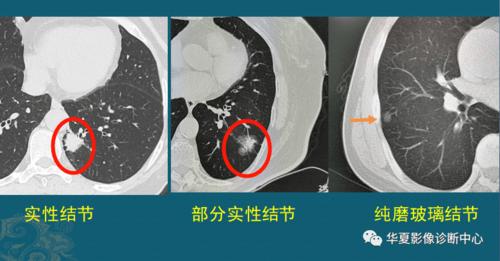

肺上有结节5个细节揭示有没有癌细胞医生教你看ct片

一起来看片~5分钟找到"肺部小结节"

肺结节ct图片

肺磨玻璃结节

磨玻璃结节